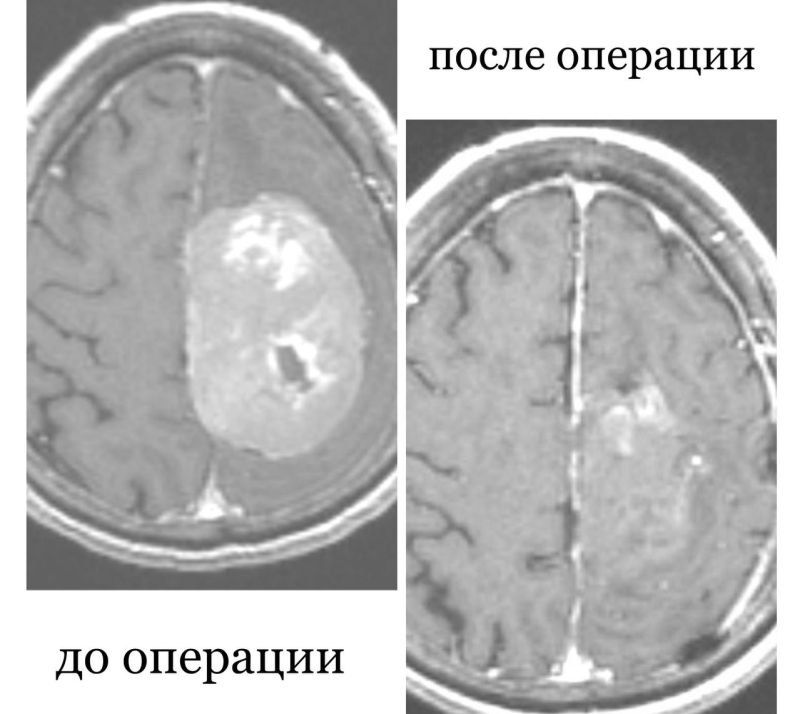

Хирургическое вмешательство по удалению крупной опухоли головного мозга прошло успешно. Практически сразу у женщины улучшилась речь, увеличилась сила в конечностях. Уже через восемь дней пенсионерку выписали домой с полным регрессом всей неврологической симптоматики. Из отделения она ушла домой на своих ногах.

Фото: РКБ